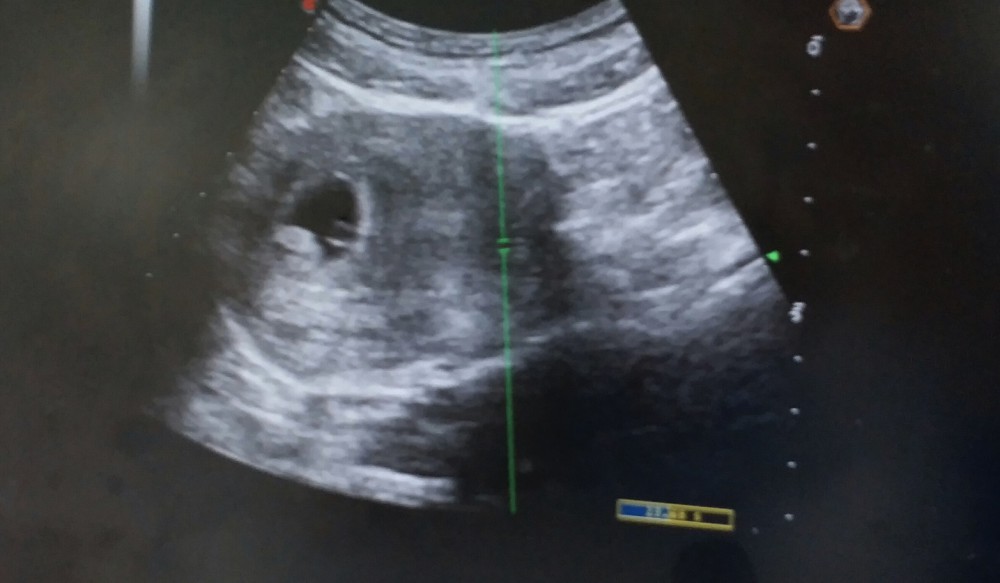

15分鐘後入醫生房照超聲波

醫生: (指向超聲波胎囊位置) 你太太懷孕6星期,有心跳,要留院觀察